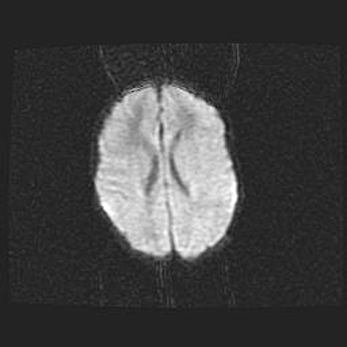

Церебральная ишемия II.

Возраст: 7 дней

Вес: 3350 г

Пол: женский

Окружность головы: 35 см

Срок гестации: 39 недель

Ишемия головного мозга – это состояние, которое развивается в ответ на кислородное голодание вследствие недостаточного мозгового кровообращения. У новорожденных она является следствием дефицита кислорода, что ведет к метаболическим расстройствам различной степени тяжести в тканях головного мозга, в том числе к развитию коагуляционных некрозов и гибели нейронов.